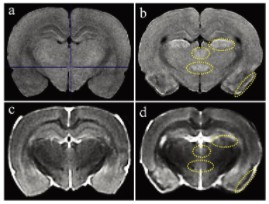

圖1顯示了T1和T2加權MRI圖像。與對照組相比, 匹羅卡品處理的動物在梨狀皮質、丘腦外側核、丘腦室周后核和大腦下丘腦后核的T1加權圖像顯示出高T1信號(圖1a和b)。在匹羅卡品處理的動物的T2加權圖像中,與對照組相比,在梨狀皮質觀察到低T2信號,對應于高T1信號區(圖1c和d)。其他3個高T1信號區的T2信號強度與對照組相當(中等強度)(圖1c和d)。